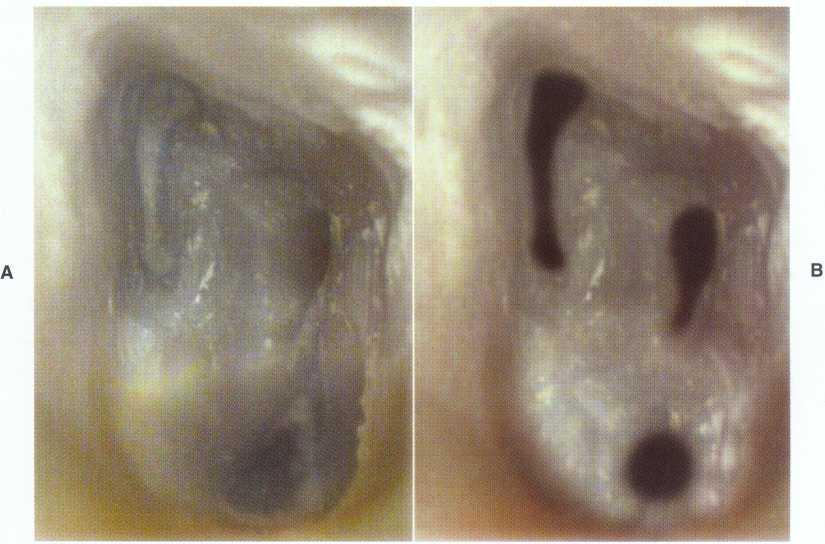

In anterior teeth the clinician must take care to remove all the coronal tissue and debris from the chamber. Material left in the chamber can cause tooth discoloration. The pulp horns are common locations for residual tissue (Figure 2-16).